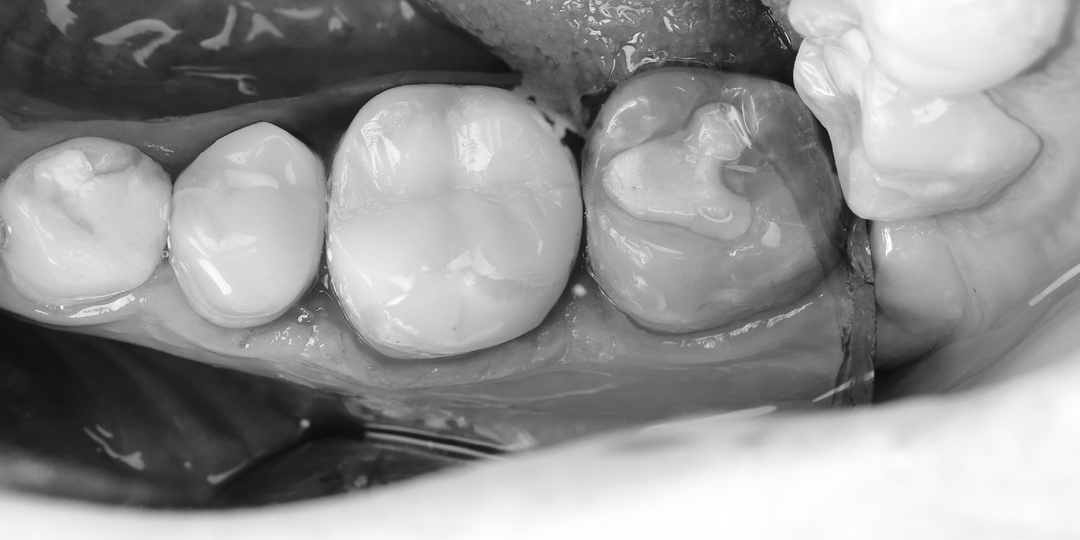

Пациенту 23 года, инсульт две недели назад и кариес до пульпы - история одного лечения

Сижу в ординаторской, никого не трогаю. Вдруг резко открывается дверь, батюшки, что я вижу - терапевт, вроде, наш, а глаза у него чужие, круглые чрезмерно. Счего бы такой перфрманс на ровном месте? Ведь только что общались с доктором, потом он пошёл принимать пациента, молодого парня 23 лет. Всё банально донельзя - нужно лечить нижнюю шестёрку, кариесом поеденную. Обычный пациент, кариес, хоть и запущенный, но ведь и не такое оставляет нас равнодушными - работа как работа. Пациент сообщил, что недавно перенёс инсульт. Пару недель как... Двадцать три года. Инсульт. И он спокойно пришёл зубы лечить. Знаете, мы такие осторожные и такие "ненавредительные", что даже дорогущие операции отменяем или переносим, если у пациента давление выше нормы и не сбивается простыми методами. А тут - инсульт, блин. У молодого парня. Две недели всего прошло! Пациент, зато - само спокойствие. Говорит - всё хорошо, лечиться пришёл, зубы лечить надо ведь. А у нас некое замешательство. Анестезия с адреналино